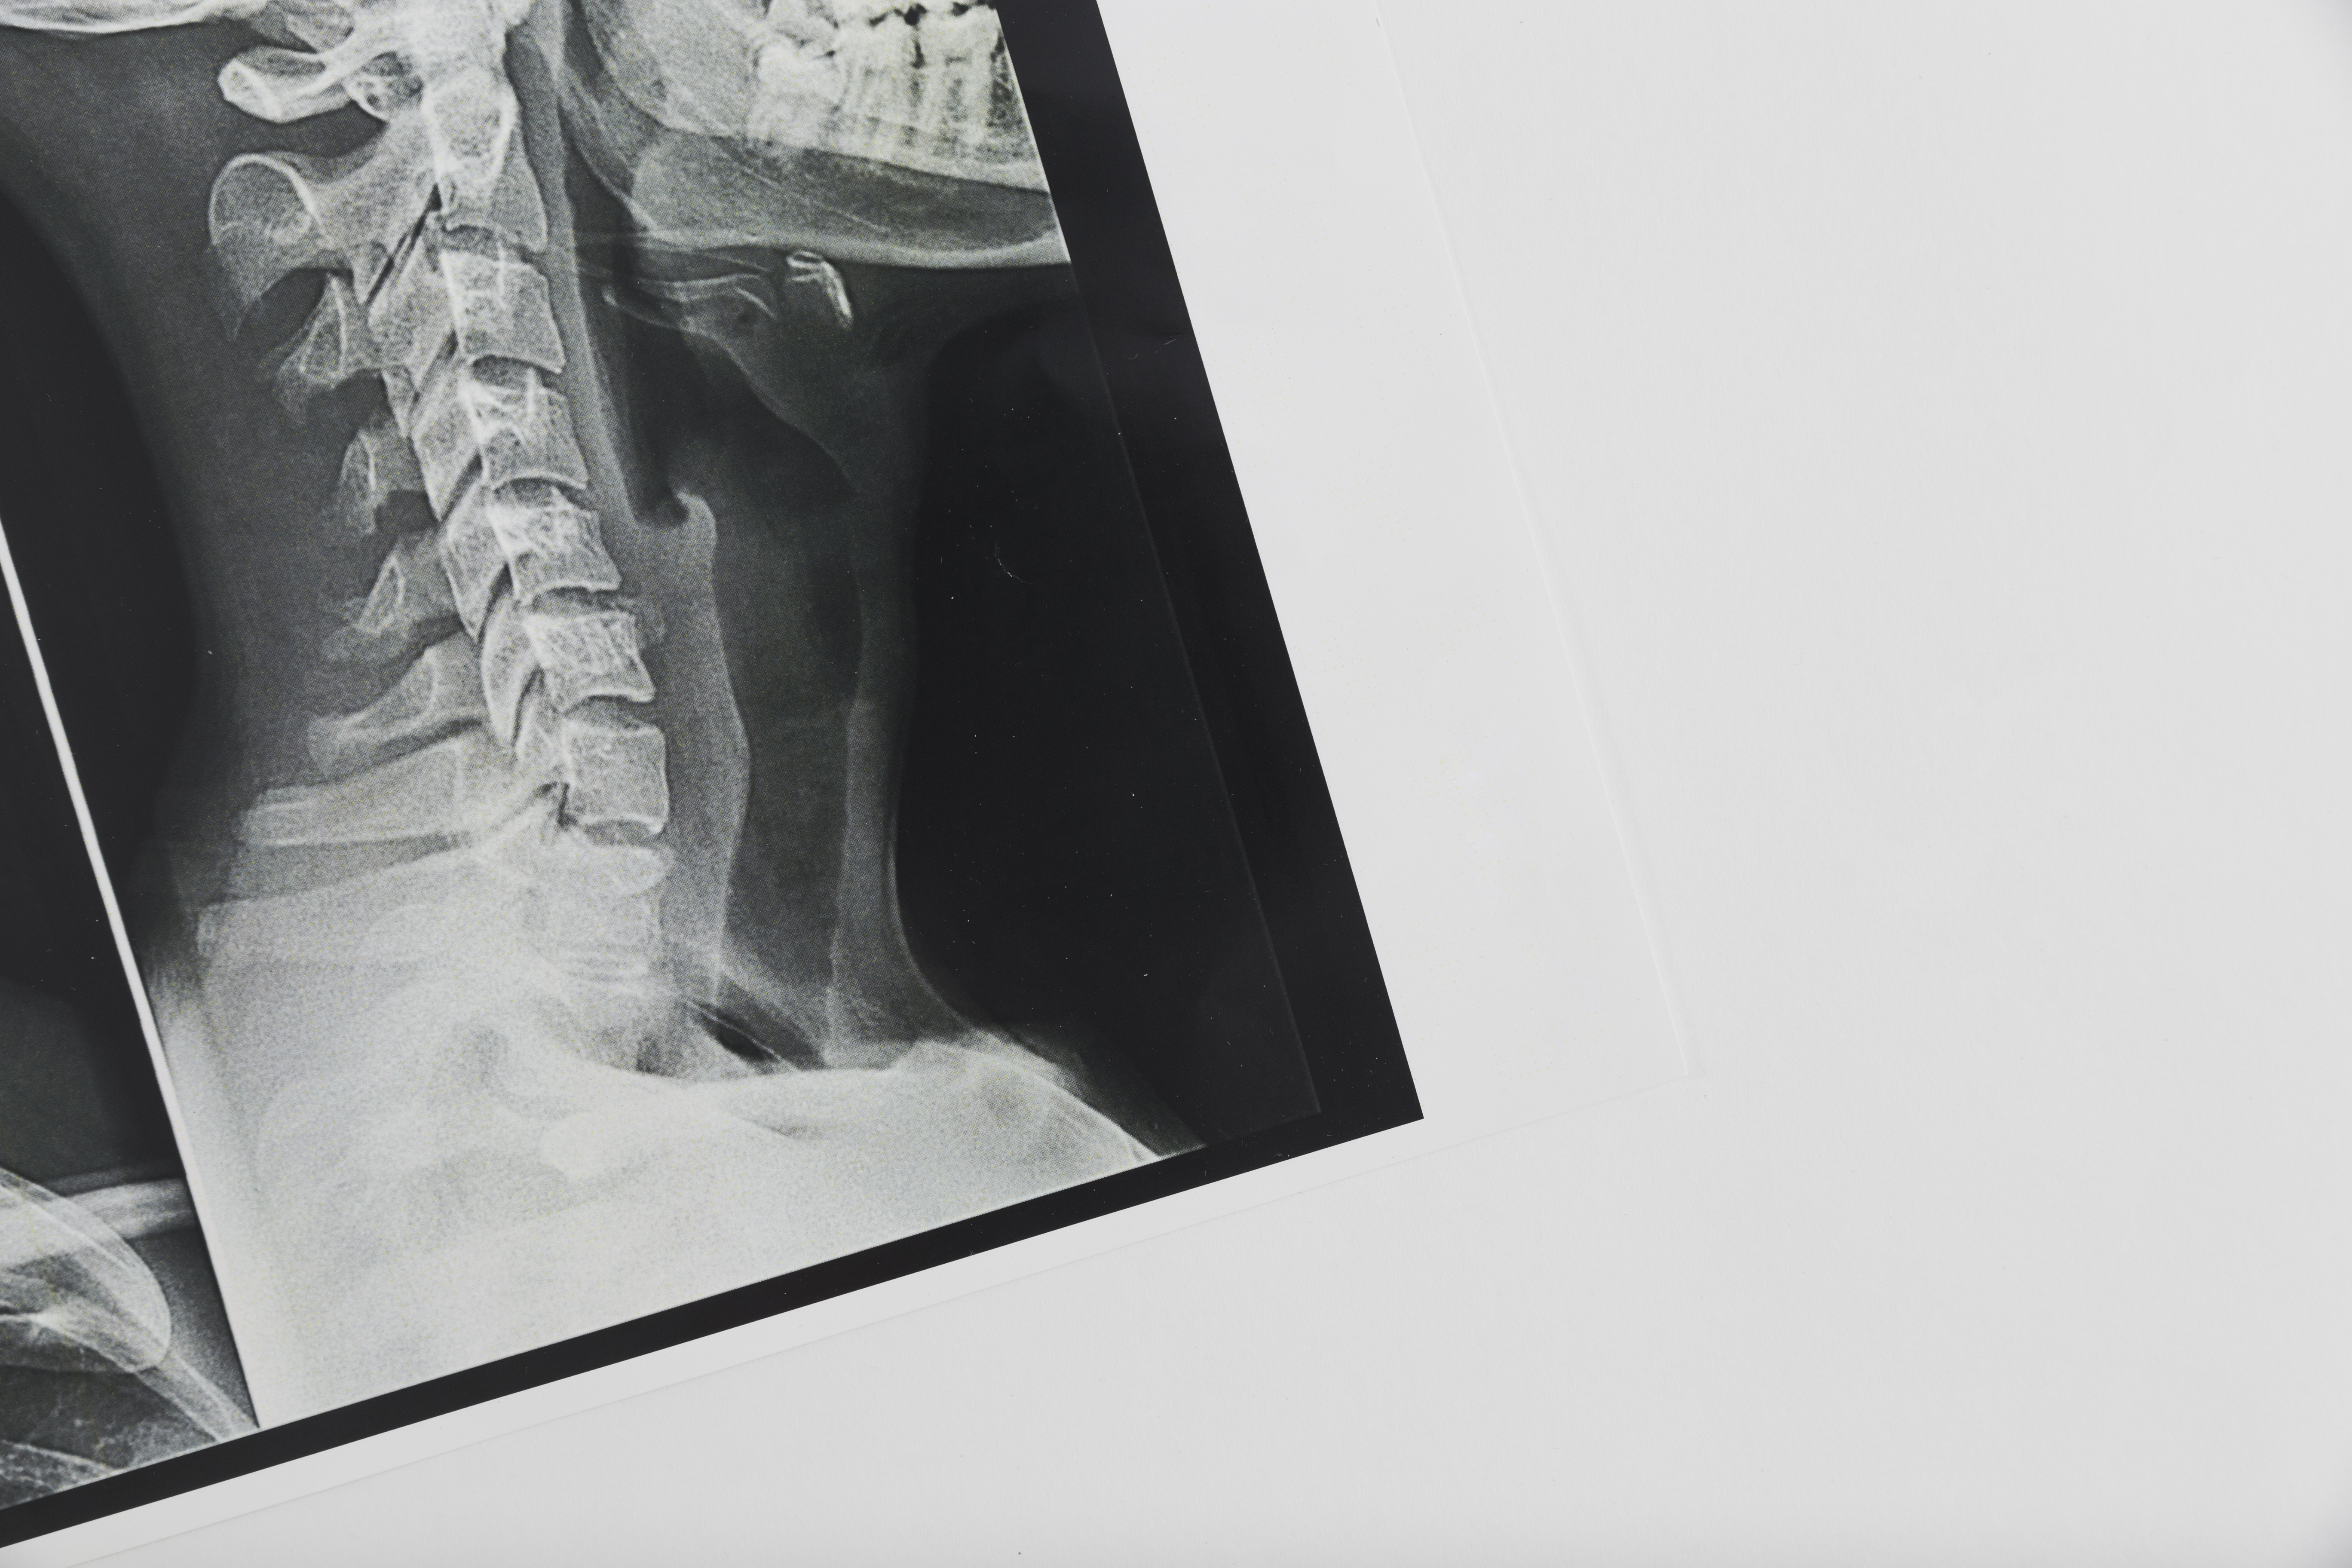

Radiologia DIGITAL RX

A radiologia DIGITAL o "RX" é muito utilizado em diagnósticos rápidos e precisos, de fácil acesso é ideal para as patologias como traumas e lesões em órgãos como o pulmão, coração e rins.